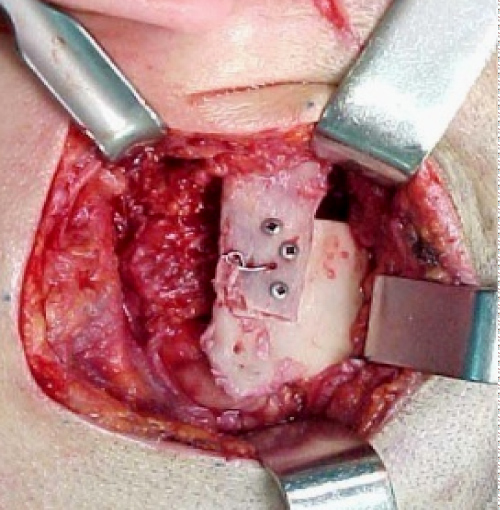

Surgical management of the TMJ ankylosis was decided in order to achieve rehabilitation of the mandible and mastication. A preauricular incision with temporal expansion performed and revealed the articular fossa and the TMJ (Figure 3). Resection of the newly formed bone mass and resection of the coronoid process was performed and the ankylosis of the TMJ was dissolved. The reconstruction of the condyle was achieved with a costo-chondral graft from the 6th rib of the patient (Figure 4), which was fixated in the ramus (Figure 5). The adjustment of the articular fossa performed next, followed by the mobilization of the temporal fascia. The temporal fascia sutured in the region replacing the articular disc and preventing new ankylosis. The function of the joint was tested and the maximum mouth opening showed nearly 40 mm (Figure 6).

Figure 5: Reconstruction of the condyle with costo-chondral graft. View Figure 5